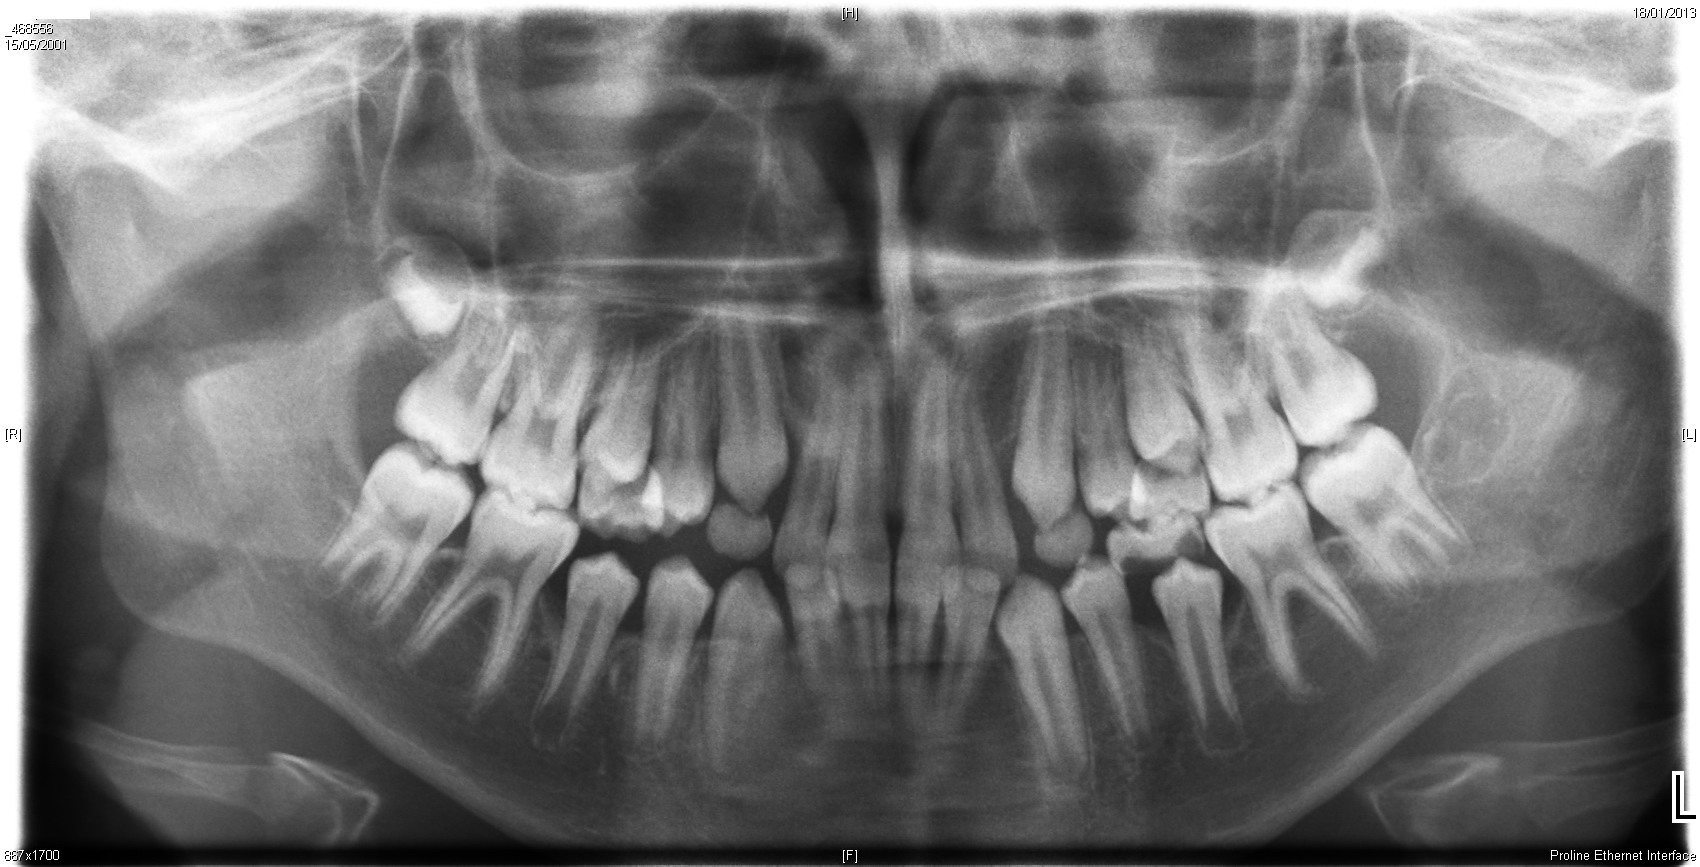

Buongiorno, avrei bisogno del vostro aiuto per capire come agire con mio figlio di quasi 12 anni. Dopo una visita di controllo dal dentista, siamo stati indirizzati dall'ortodonzista per valutare se mettere l'apparecchio o meno. Da una prima visita, richiesta l'ortopanoramica che allego, mi viene detto che c'è da spendere (testuali parole). Al momento di fissare la terapia definitiva, per motivi personali il dottore disdice l'appuntamento e io vado di corsa da un altro ortodonzista consigliato perchè data l'età di mio figlio penso di essre pure in ritardo (pulce messa dal primo ortodonzista). Quest'ultimo invece mi dice che non devo fare proprio niente, che il bambino è messo bene e che casomai ci si vede alla fine dell'estate, guardandomi come fanno i dottori quando secondo loro i genitori esagerano nel preoccuparsi... potete per favore confermarmi il vostro parere? Grazie mille in anticipo.

Stando solo alle radiografie che ha postato, sarei propenso ad una strategia attendista, ma è chiaro che dipente tutto anche da una visita dal vivo e soprattutto dal grado di allineamento che si vuole raggiungere. Cordiali saluti.

Sembra una situazione di biprotrusione funzionale da postura linguale errata ingravescente con difetto degli orbicolari. Siamo già al termine massimo della attesa, anzi in gravissimo ritardo (andava trattato a 6 anni). Lo faccia vedere subito. Tenga presente che nessuno (me compreso) può fare una diagnosi solo VEDENDO le radiografie (infatti io vado ad immaginazione, glielo garantisco, come chiunque altro le risponderà qui): queste vanno usate per fare una analisi complessa che si chiama CEFALOMETRIA (legga sul sito e sui miei siti cosa è): scelga solo dentisti che non si limitano a guardare queste rx, ma che ne ricavano una vera analisi della struttura ossea, ovvero la cefalometria.

Gentile Signora, concordo assolutamente con la risposta del Dott. Passaretti, senza cefalometria ortodontica non è possibile impostare nessun trattamento ortognatodontico. A questo punto, considerato che suo figlio ha già praticamente completato la permuta dei decidui ed ha già in arcata i settimi, attendere ulteriormente non avrebbe senso. Prenda appuntamento da uno specialista preparato per iniziare il trattamento in breve tempo. Cordialmente

Il tratto cervicale del rachide mi sembra ( dal poco che si vede) abbia perso qualcosa della naturale lordosi ( curvatura fisiologica in avanti) e questo sembrerebbe dare ragione a ciò che scrive il dr. Passaretti ( funzionalità linguale). Approfondisca.

Gentile sig.ra, per dare un parere ci servono almeno le foto dei denti in visione frontale e laterale, con gli elementi a disposizione, propenderei più a quanto detto dal secondo collega che ha visitato suo figlio, cioè non mi pare di vedere grossi problemi, e comunque non mi fiderei mai di un medico che esordisce " qui c'è tanto da spendere" ma che siamo al mercato! a questo punto , tanto ormai, non c'è più tanta fretta, visto che non è più in età per una terapia ortopedica-funzionale che avrebbe risolto gli eventuali problemi a monte, e che comunque si deve montare un apparecchio fisso, e probabilmente il collega le ha detto di tornare dopo l' estate, così sarebbero scesi in arcata gli ultimi denti definitivi, faccia una terza visita, con ortodontista esperto, e poi decida, se vuole io le posso dare un parere senza nessun impegno.

Gentile Signora, dalle radiografie che ha postato é evidente una malocclusione con profilo biprotruso dei gruppi anteriori da componente linguale. La rettilineizzazione del tratto cervicale della colonna indica un'alterazione posturale ed aumenta il sospetto di deglutizione disfunzionale. Una visita gnatologica é indispensabile per confermare la diagnosi. Il periodo ottimale per curare tale patologia é durante la permuta dentaria, ovvero tra i 6 ed i 12 anni, per cui le consiglio di non attendere altro tempo per portarlo da uno Gnatologo e di affidarlo alle sue cure. Cordiali saluti.

Non mi sembra ci siano grandi problemi. Ci mandi anche le fotografie dei rapporti dentali. Cordialmente